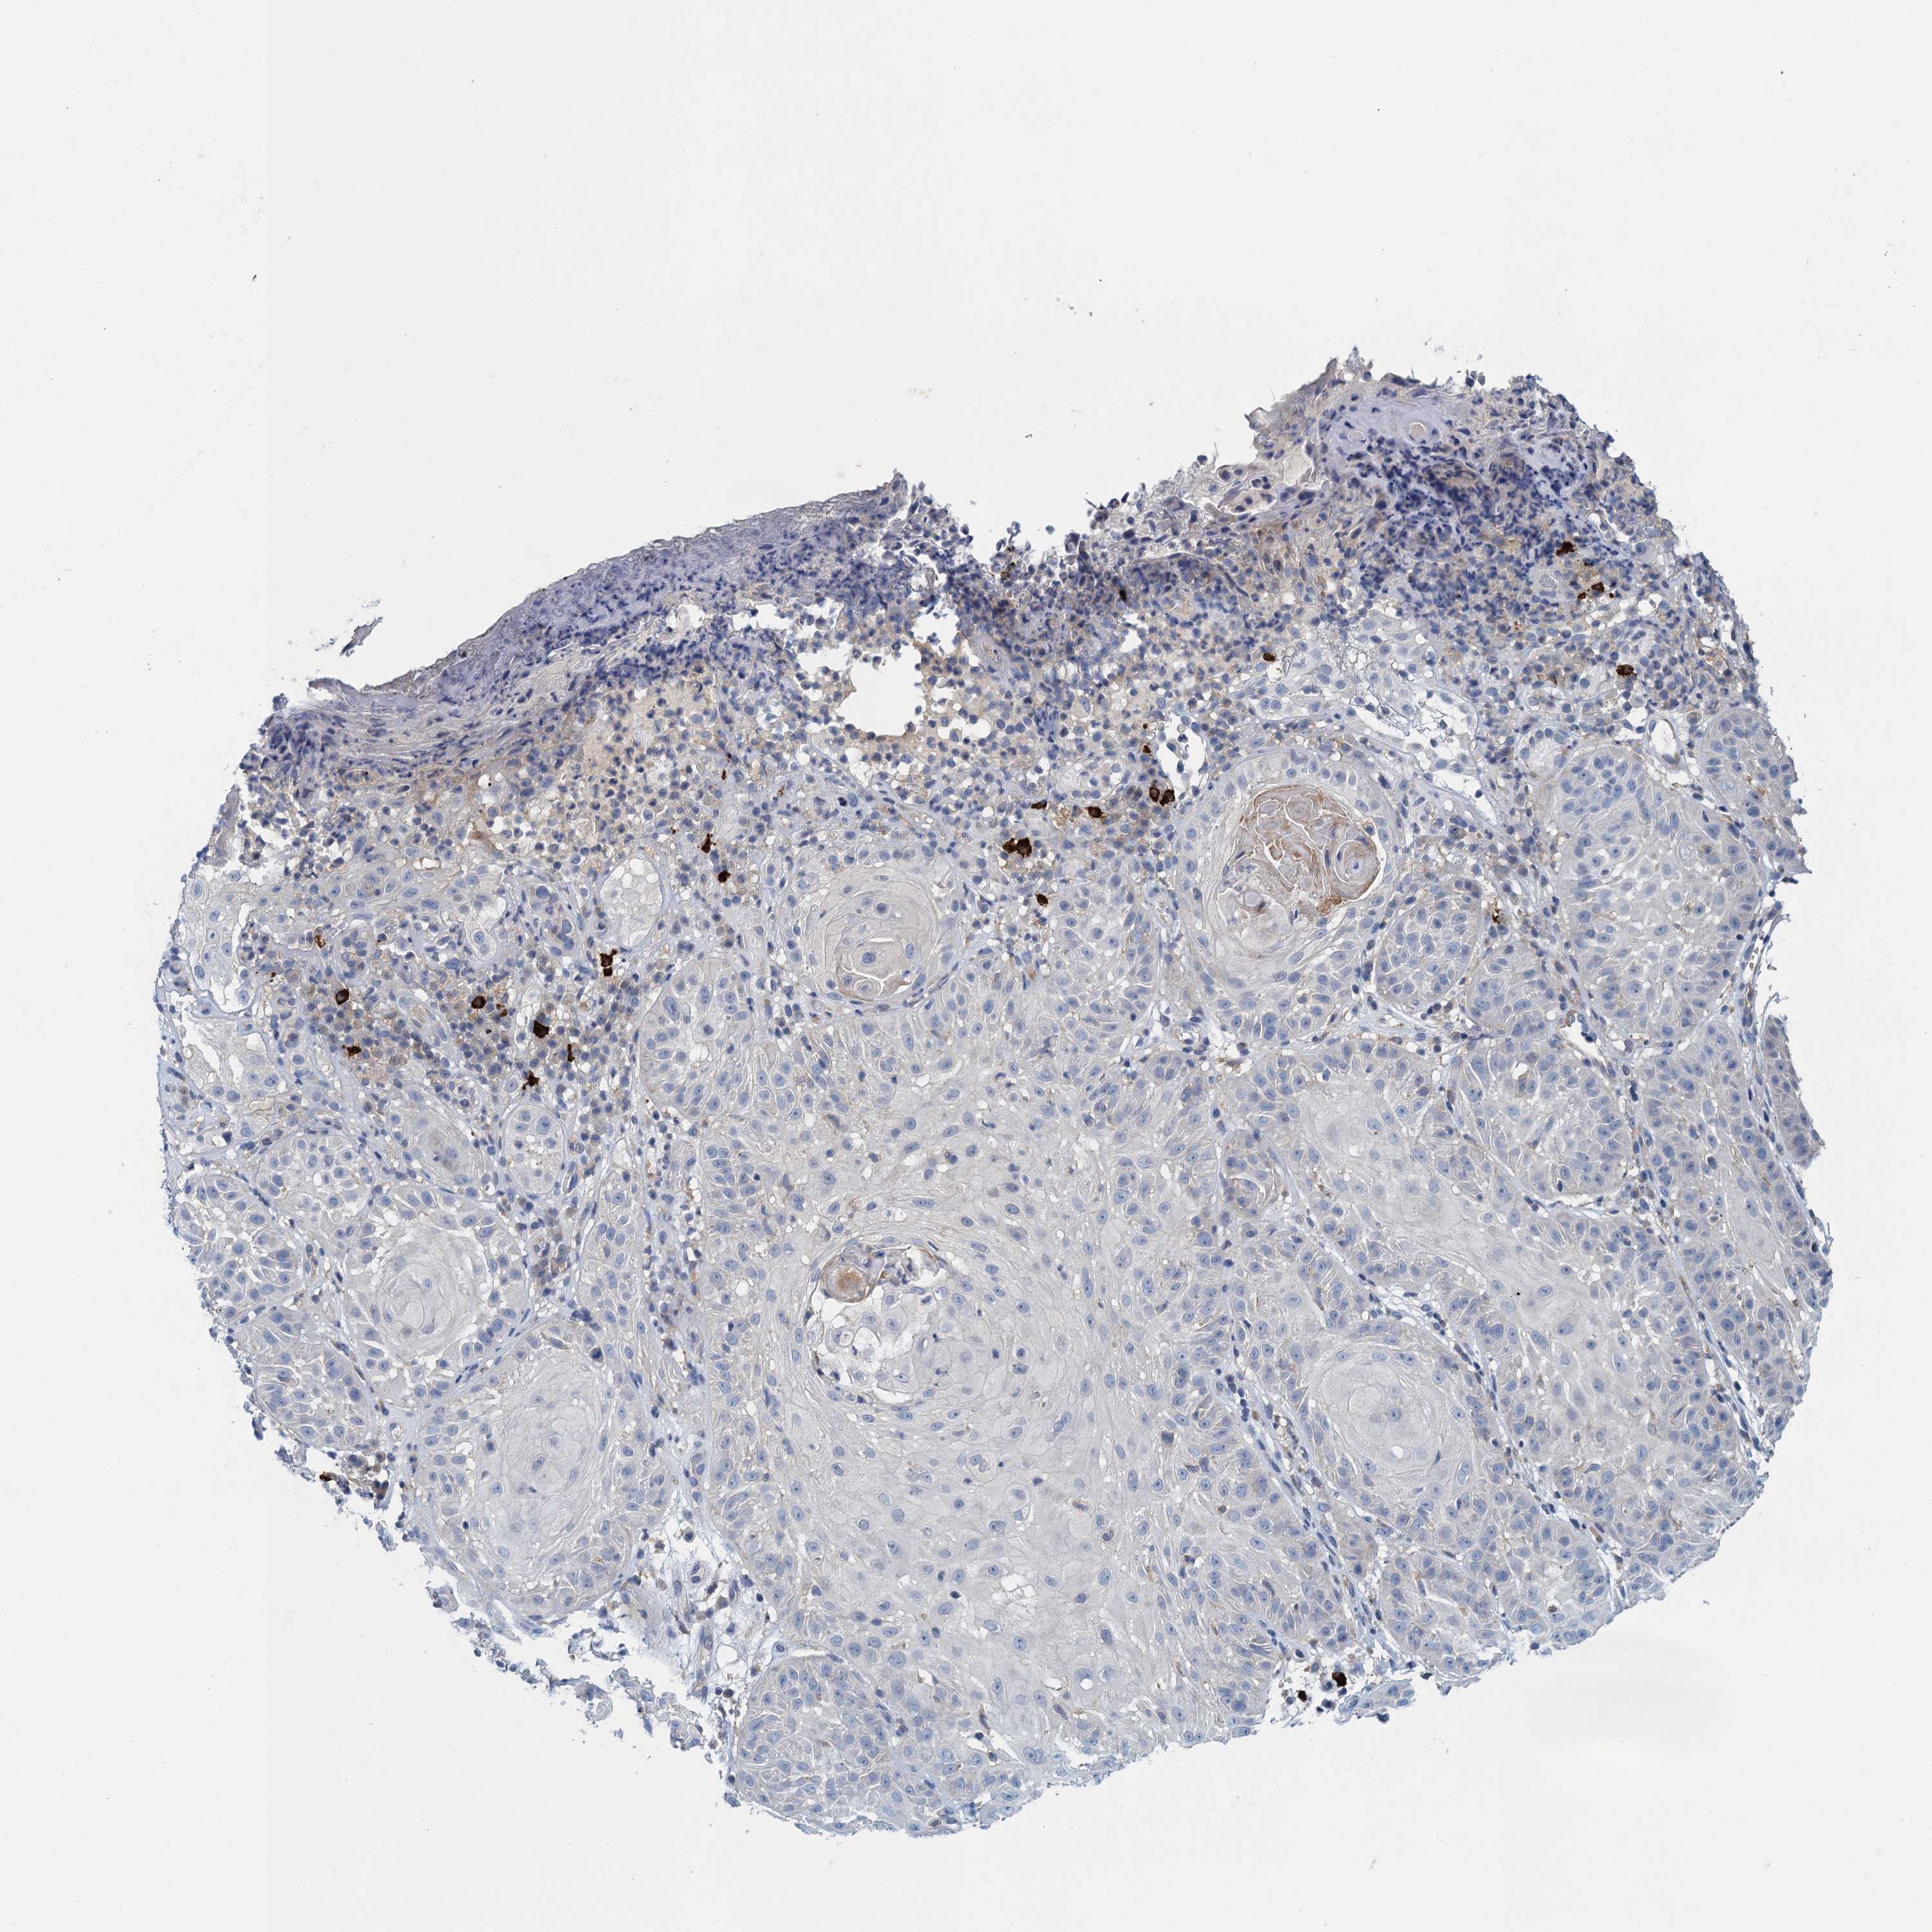

SKIN CANCER - Protein expressioni

A mouse-over function shows sample information and annotation data. Click on an image to view it in a full screen mode. Samples can be filtered based on level of antibody staining by selecting one or several of the following categories: high, medium, low and not detected. The assay and annotation is described here.

Antibody staining in the annotated cell types in the current human tissue is reported as not detected, low, medium, or high, based on conventional immunohistochemistry profiling in selected tissues. This score is based on the combination of the staining intensity and fraction of stained cells.

Each image is clickable and will lead to virtual microscopy that enables deeper exploration of all samples and also displays staining intensity scores, fraction scores and subcellular localization as well as patient and tissue information for each sample.

Antibody HPA039490

Basal cell carcinoma